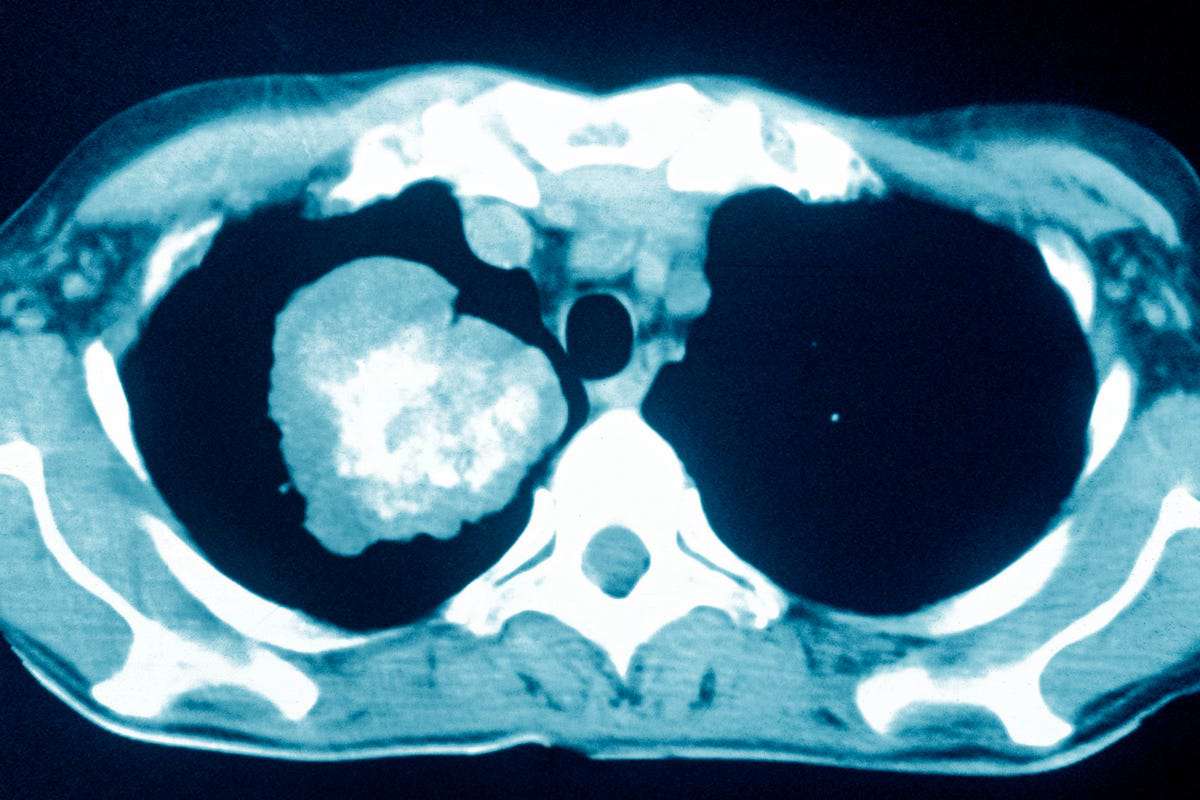

Low Dose CT is a special form of x-ray that allows for three-dimensional images of your lungs to detect lung cancer at a stage it may not be visible with standard x-rays. The good news is the exam takes 1-2 minutes to complete and is completely non-invasive.